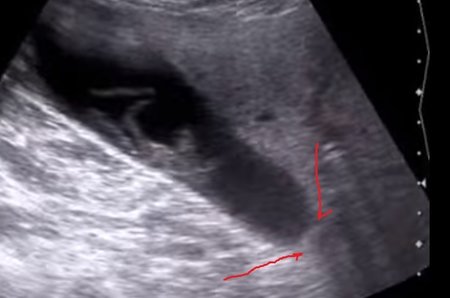

Нарисуйте нам на кадре из клипа.servik писал(а):не скрывал, вроде на статике 28-29 сек видноKsV писал(а):Конкремент в шейке не показан в клипе. Очень важный момент преднамеренно скрыт автором. .

KsV писал(а):Нарисуйте нам на кадре из клипа.servik писал(а):не скрывал, вроде на статике 28-29 сек видноKsV писал(а):Конкремент в шейке не показан в клипе. Очень важный момент преднамеренно скрыт автором. .

Ни на видео, ни в кадре - нигде не видно блокирующего конкремента.

есть информация по случаю - флегмонозный холецистит, с формированием парапузырного инфильтрата, конкремент вклиненный в гартманов карман и пузырный проток Мирризи 1